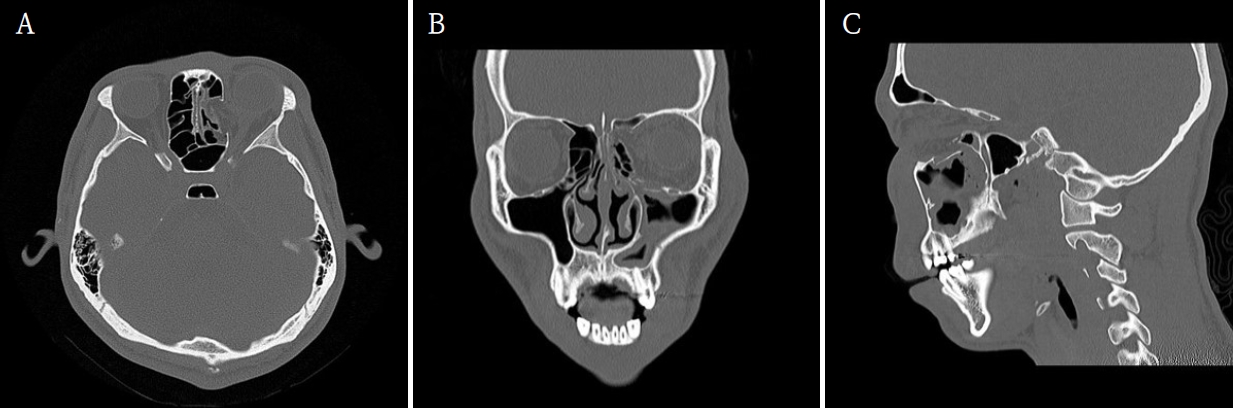

Orbital inferior and medial wall repair via the paranasal sinus: A case report

Jinlee Kim, Haemin Kim, Jaeyoung Ryu, Seunggon Jung, Min-Suk Kook, Chung Man Sung, Hyung Chae Yang, Hong-Ju Park

J Korean Dent Assoc.

2025;63(11):353-358. Published online November 30, 2025